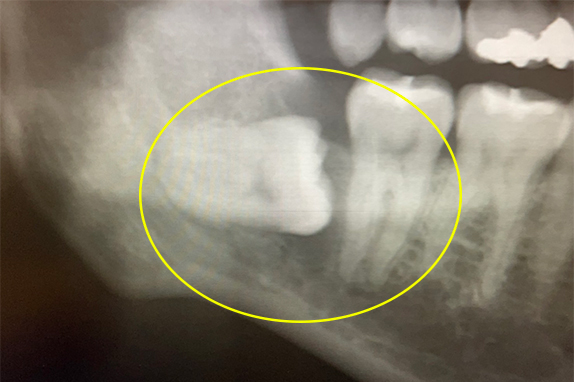

CASE 03 歯周再生療+PDT療法

-

- 主訴

- 右下奥歯から膿が出る(30代女)

-

- 回数期間

- 5回 約8ヶ月

-

- 治療法

- 歯周再生療法+PDT療法

-

- 治療費用

- 約20万円(税抜)

右下奥歯から膿が出るという主訴で来院。歯周再生療法、PDT療法で改善したケースです。

<リスク・副作用>

治療後は痛み、腫れ、痺れなどの副作用が生じる場合があります。症状が再発する可能性があります。